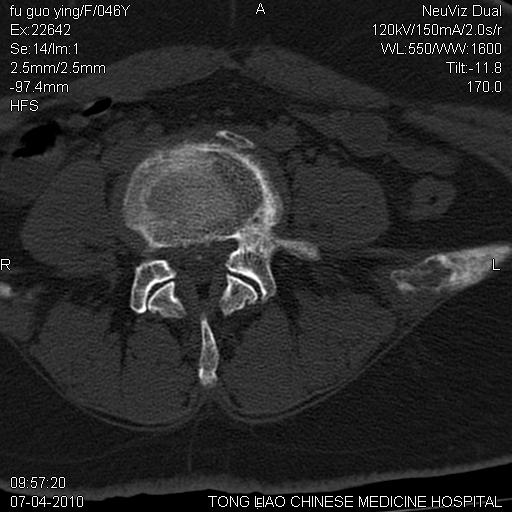

标题: CT27489:患者腰疼,其余椎体未见异常! [打印本页]

标题: CT27489:患者腰疼,其余椎体未见异常!

女性46岁,左髂骨溶骨性破坏+软组织肿块,考虑转移瘤,腰椎为退变/增生硬化/软骨下骨囊变。